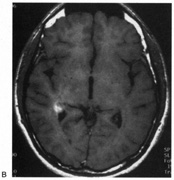

Fig. 15. Bilateral incomplete hemianopia. A 69-year-old man with decreased vision after prostate surgery. A. Fields show remaining central parafoveal vision with some sparing of inferior left quadrant. Note how the defect respects the vertical meridian. B. MRI shows bilateral medial occipital infarction, with sparing of the occipital poles, accounting for the macular-sparing bilaterally. (Courtesy of Dr. Lucia Vaina.)

Cerebral Blindness